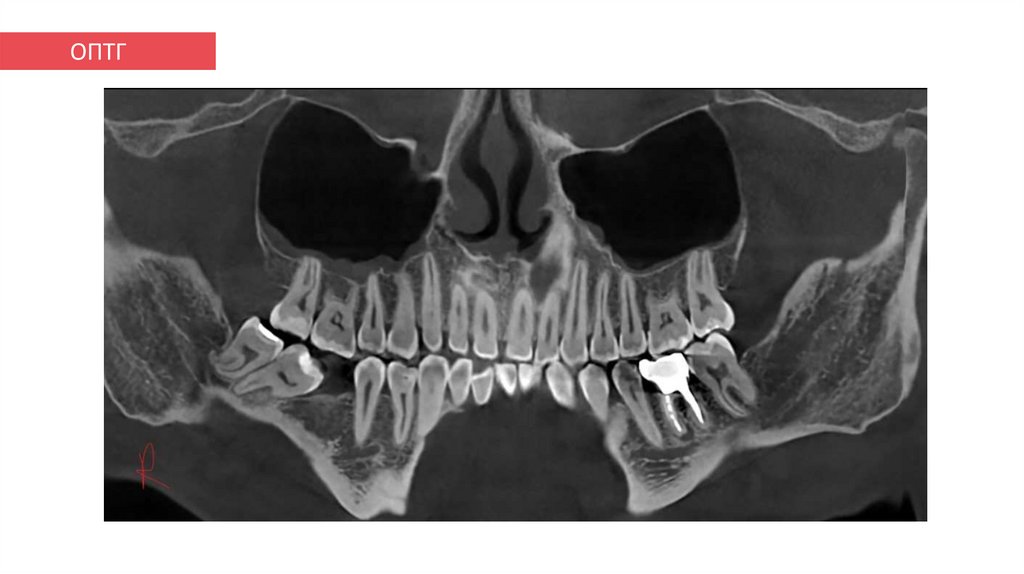

ОПТГ

10. ОПТГ